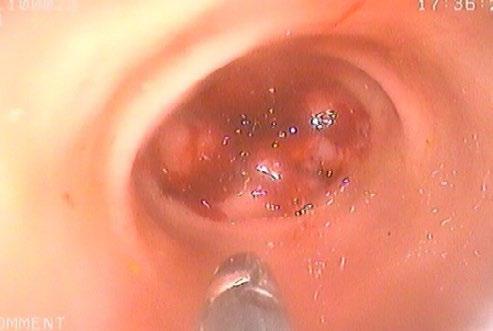

We considered the lesion to be accessible to colonoscopic biopsy, and so this was conducted, in an attempt to obtain a definitive diagnosis.

The lesion was readily accessible to endoscopic biopsy but unfortunately the results were inconclusive. Lymphoma was considered unlikely, and there was no indication of any other neoplasia.